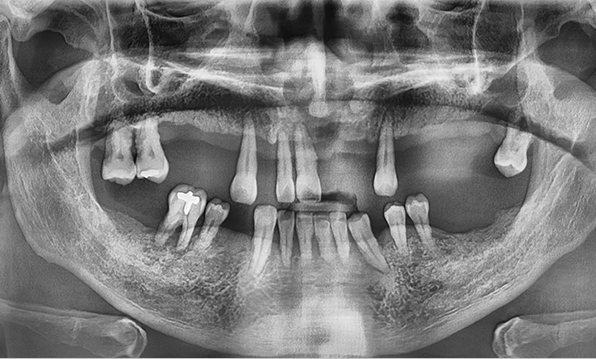

Case 04

Before After